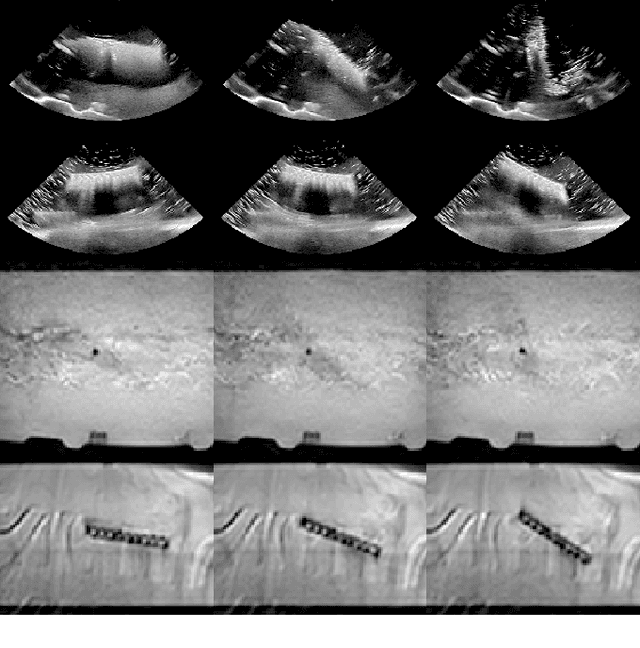

Abstract:Detecting acoustic shadows in ultrasound images is important in many clinical and engineering applications. Real-time feedback of acoustic shadows can guide sonographers to a standardized diagnostic viewing plane with minimal artifacts and can provide additional information for other automatic image analysis algorithms. However, automatically detecting shadow regions is challenging because pixel-wise annotation of acoustic shadows is subjective and time consuming. In this paper we propose a weakly supervised method for automatic confidence estimation of acoustic shadow regions, which is able to generate a dense shadow-focused confidence map. During training, a multi-task module for shadow segmentation is built to learn general shadow features according based image-level annotations as well as a small number of coarse pixel-wise shadow annotations. A transfer function is then established to extend the binary shadow segmentation to a reference confidence map. In addition, a confidence estimation network is proposed to learn the mapping between input images and the reference confidence maps. This confidence estimation network is able to predict shadow confidence maps directly from input images during inference. We evaluate DICE, soft DICE, recall, precision, mean squared error and inter-class correlation to verify the effectiveness of our method. Our method outperforms the state-of-the-art qualitatively and quantitatively. We further demonstrate the applicability of our method by integrating shadow confidence maps into tasks such as ultrasound image classification, multi-view image fusion and automated biometric measurements.